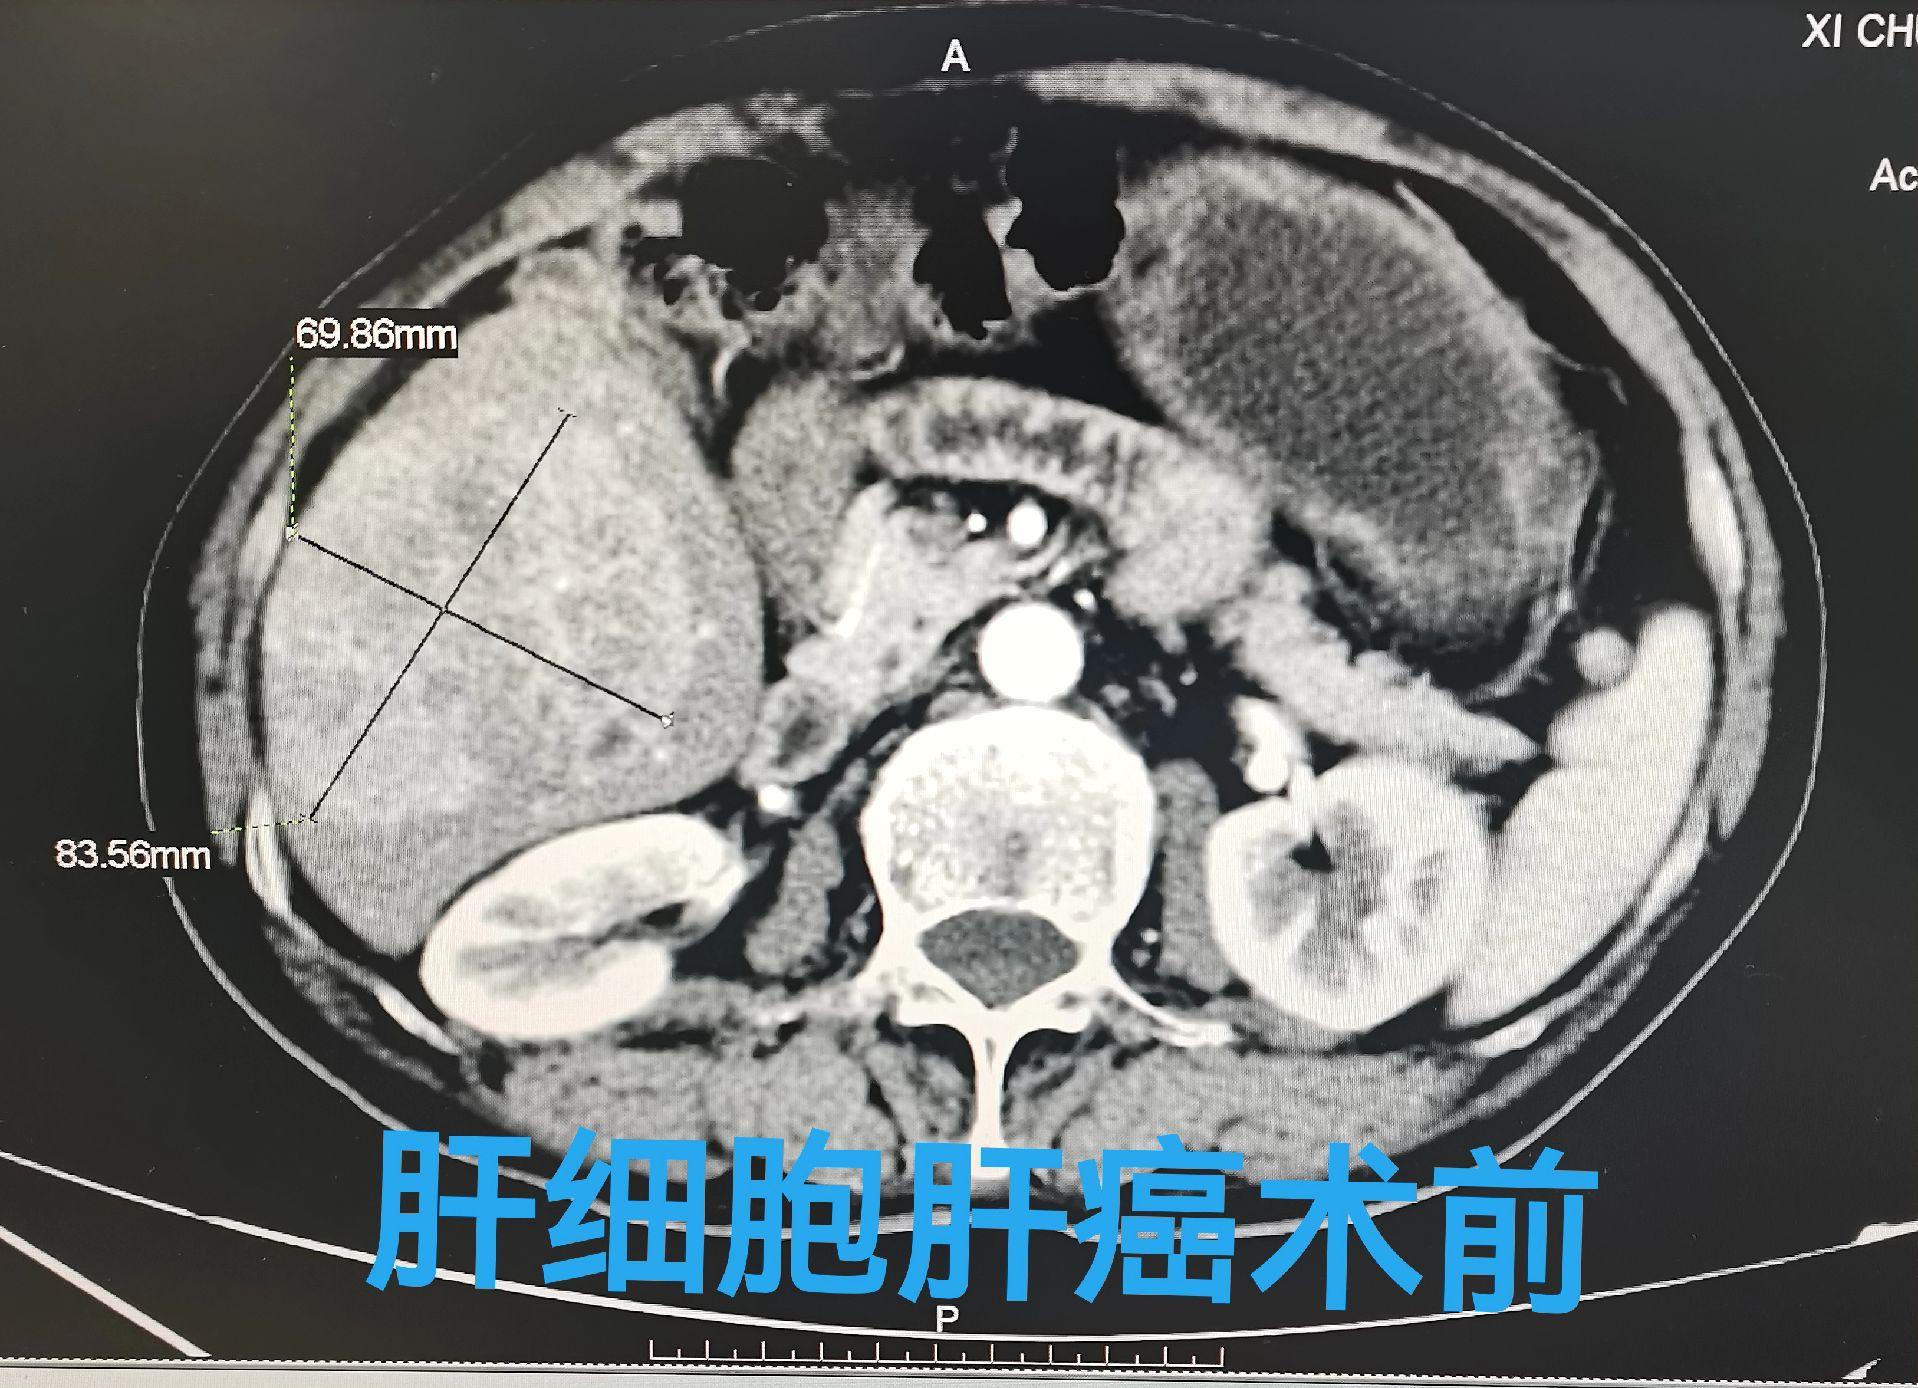

一例肝细胞肝癌患者,肿瘤直径约85mm,经介入载药微球栓塞,术后肿瘤完全坏死无活性。甲胎球蛋白降至正常。介入治疗疗效确切,安全可靠,创伤小回恢复快!